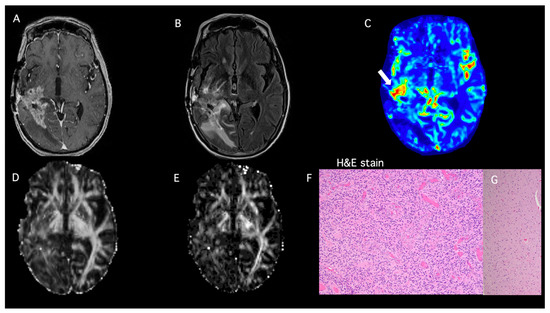

- Patient 2

| Patient ID | DTI-FA | DTI-CL | DSC-rCBVmax | PP-Value TP ≥ 50% PsP < 50% | Histopathology | Modified RANO |

|---|---|---|---|---|---|---|

| 2 | 0.15 | 0.05 | 7.94 | 99% | TP | |